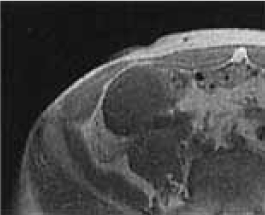

Contrast enhanced CT: We show it, but there are no mild augmentation effects in the internal augmentation effect to wall. We contact with a right external iliac artery, but cannot point out the clear invasion (Figure 2).

Figure 2. Contrast enhanced CT